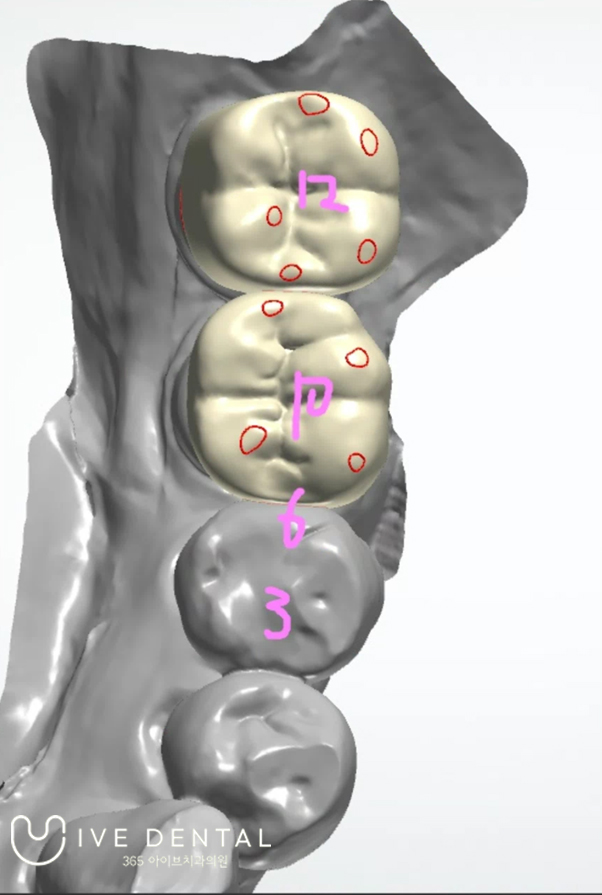

실제 작업을 하는 사진인데요. 이런 식으로 3D 프로그램을 이용하여 환자분의 구강 상태에 맞는 보철물을 직접 제작해 드리고 있습니다.

아무래도 기공소에 맡기는 거보다 수술한 원장인 제가 디자인하는 것이 환자분의 구강 상태에 딱

맞는 보철물을 제작해 드릴 수 있어 한분 한분 직접 디자인해 드리고 있습니다.

실제 위 환자분의 임플란트를 제가 직접 디자인 한 사진입니다.

인접 치아와의 배열과 씹기 편한 교합 등을 생각하고 정밀하게 디자인하여

환자분이 쓰기 편하게 임플란트를 만들어 드리고 있습니다.